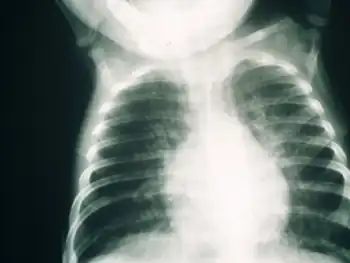

SCID patients are usually affected by severe bacterial, viral, or fungal infections early in life and often present with interstitial lung disease, chronic diarrhea, and failure to thrive.[3] Ear infections, recurrent Pneumocystis jirovecii (previously carinii) pneumonia, and profuse oral candidiasis commonly occur. These babies, if untreated, usually die within one year due to severe, recurrent infections unless they have undergone successful hematopoietic stem cell transplantation or gene therapy in clinical trials.[6]

Early diagnosis of SCID is usually difficult due to the need for advanced screening techniques. Several symptoms may indicate a possibility of SCID in a child, such as a family history of infant death, chronic coughs, hyperinflated lungs, and persistent infections. A full blood lymphocyte count is often considered a reliable manner of diagnosing SCID, but higher lymphocyte counts in childhood may influence results. Clinical diagnosis based on genetic defects is also a possible diagnostic procedure that has been implemented in the UK.[12]